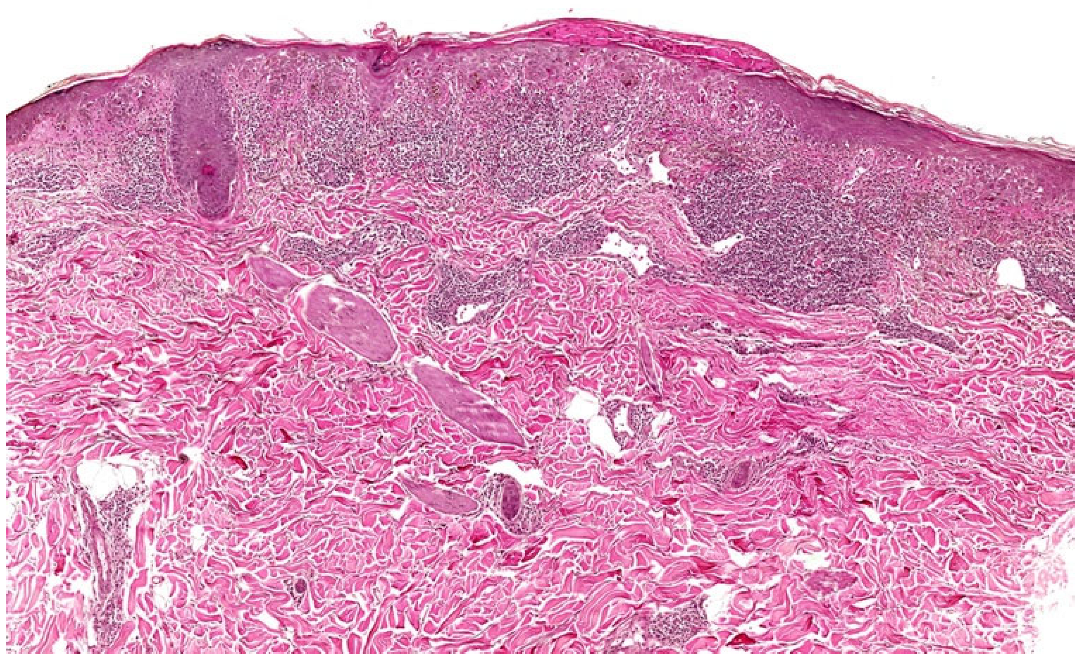

3.2.1. Hypertrophic Lichen Planus (HLP)

| HLP | Thickened, verrucous, purple-red, plaque/nodule | Wedge-shaped | Pseudoepitheliomatous hyperplasia, endophytic well-differentiated squamous epithelium extending not beyond the superficial dermis | Irregular | Present | Basal cell vacuolar alteration; thickening of collagen fibres in the papillary dermis | Longer mean duration and often unremitting compared with LP |